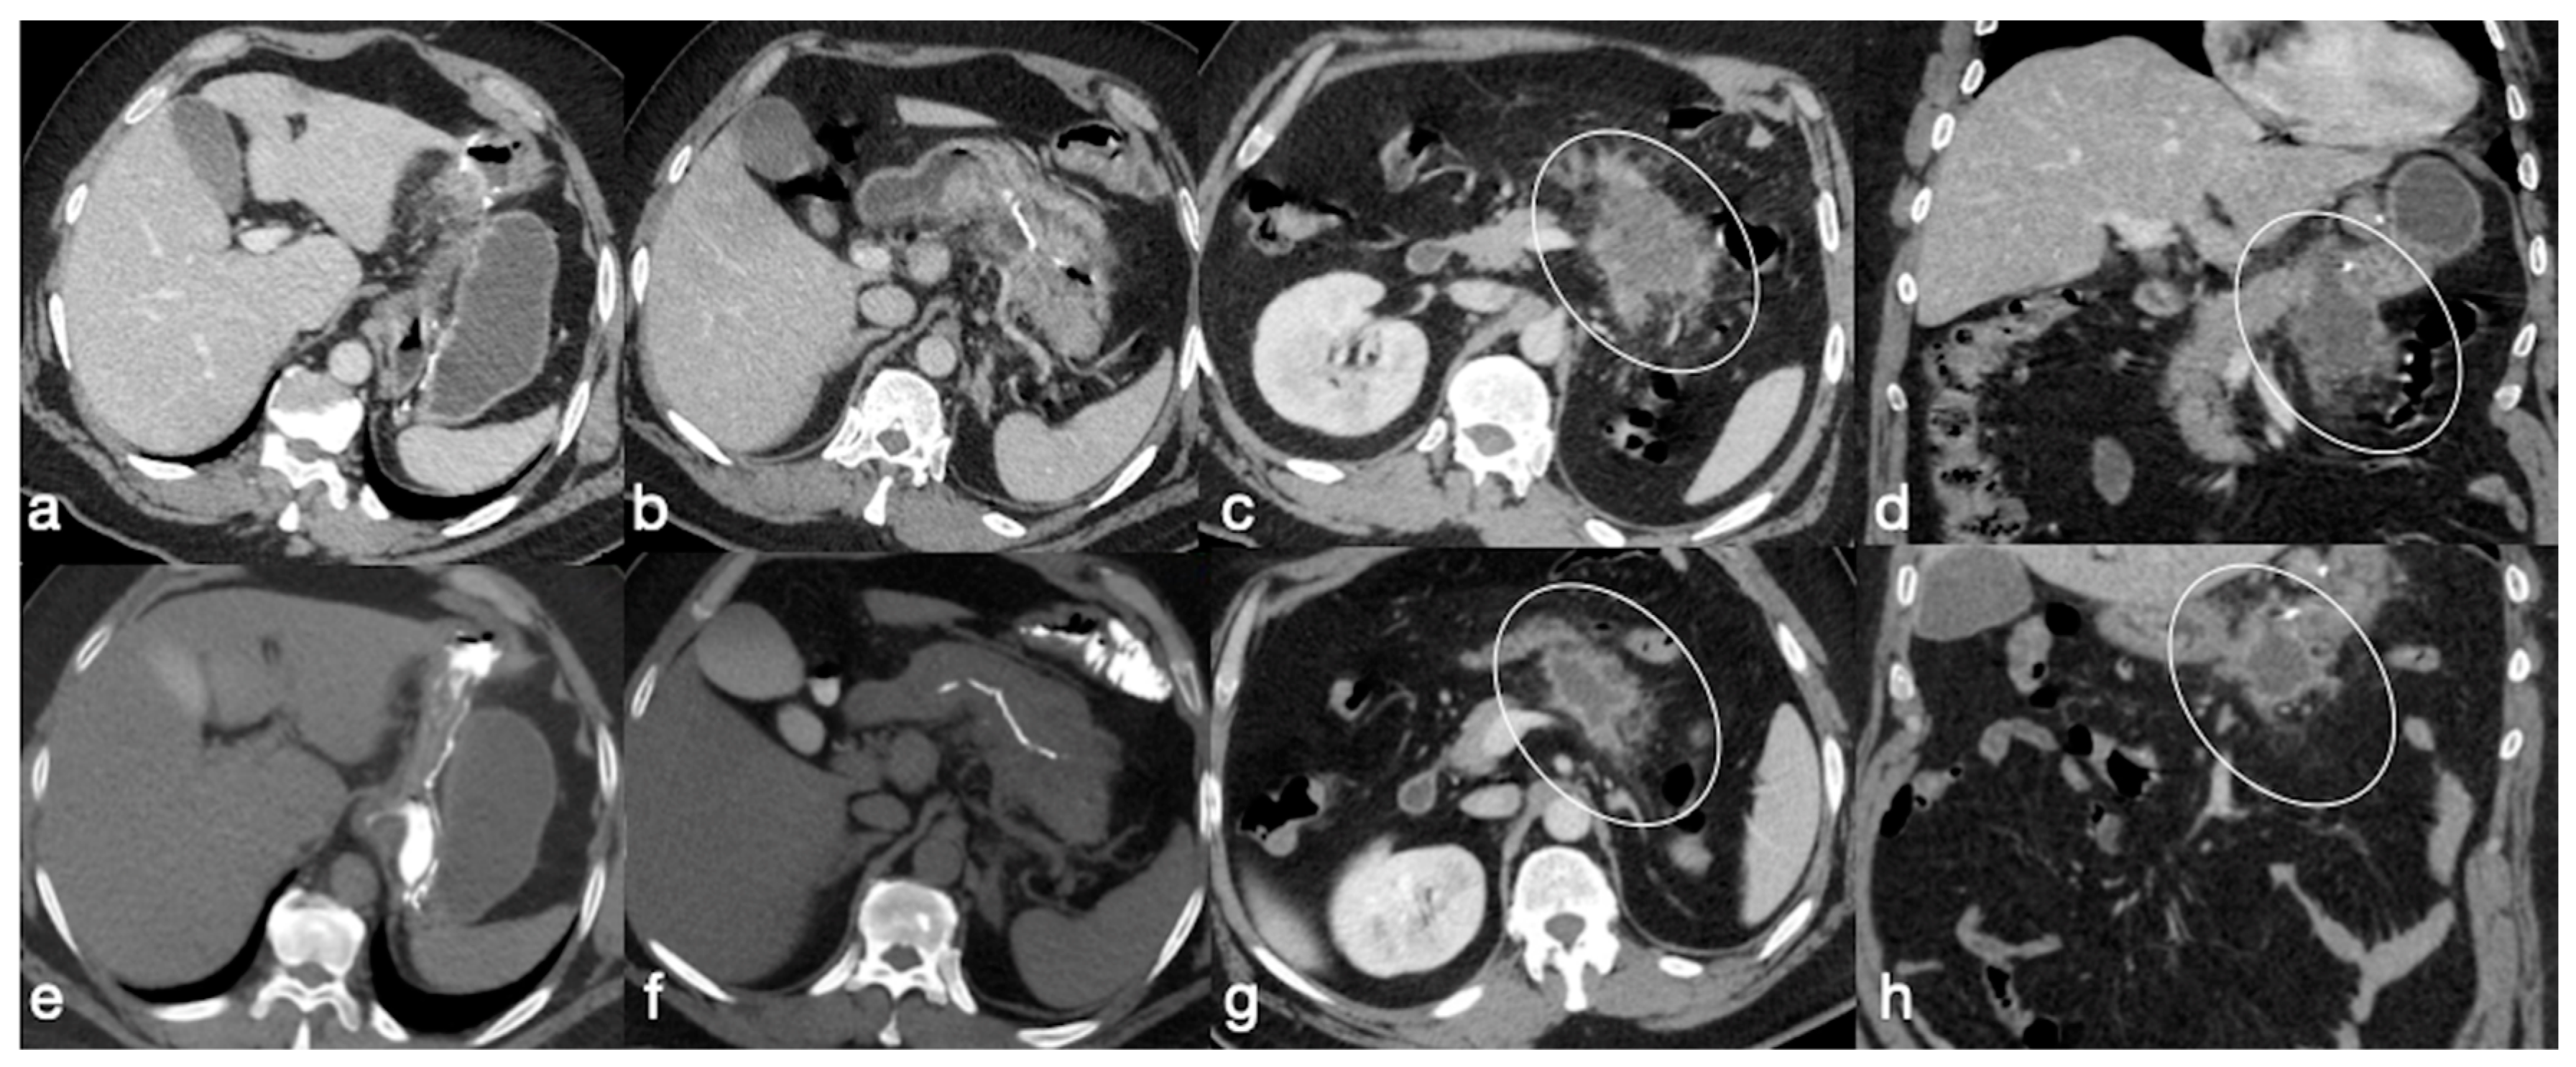

Figure 22. Patient 4. Leak from excluded stomach after gastric bypass. A 47-year-old male patient with previous gastric bypass was complaining of abdominal pain and fever. Note the surgical sutures of the gastric bypass (a,b, axial view) and in (c) the fluid collection (circle) that seems to arise from the excluded stomach (d, circle) and not supplied after the oral contrast administration (e,f axial views). According to the interventional radiologist and the surgeon, it was decided to conservatively treat the patients and at the CT follow-up 13 days later the fluid collection was reduced (g, axial view; h, coronal view, arrows).